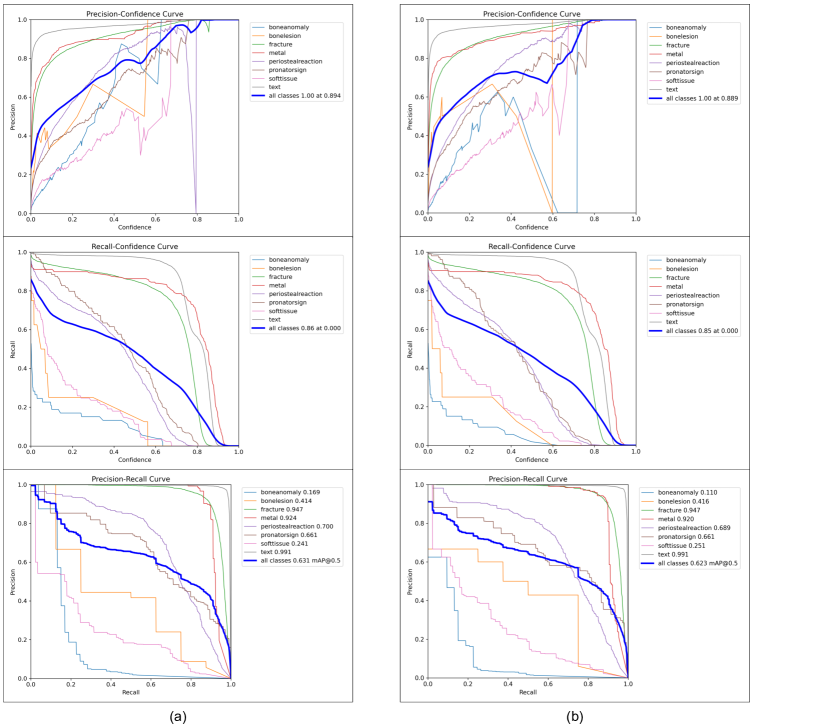

In order to demonstrate the positive effect of our training method on the performance of YOLOv8 model, we conduct an ablation study on YOLOv8s model by calculating each evaluation metric for each class, as shown in Table 2. Among all classes, YOLOv8s model has good accuracy in detecting fracture, metal and text, with mAP 50 of each above 0.9. On the opposite, the detection ability of bone-anomaly is poor, with mAP 50 of 0.11. Therefore, we increase the contrast and brightness of X-ray images to make bone-anomaly easier to detect. Table 3 presents the predictions of YOLOv8s model using our training method for each class. Compared with YOLOv8s model, the mAP value predicted by the model using our training method for bone-anomaly increased from 0.11 to 0.169, an increase of 53.6%. Figure 5 also shows that our model has a better performance in detecting bone-anomaly, which enables the improvement of the overall model performance. From the ablation study presented above, we demonstrate that the model performance can be improved by using our training method (data augmentation). In addition to the data enhancement, researchers can also improve model performance by adding modules such as the Convolutional Block Attention Module (CBAM) [70].

Experimental Results

Before training our model, in order to choose an optimizer that has a more positive effect on the model performance, we compare the performance of models trained with the SGD [74] optimizer and the Adam [73] optimizer. As shown in Table 4, using the SGD optimizer to train the model requires less epochs of weight updates. Specifically, for YOLOv8m model with an input image size of 1024, the model trained with the SGD optimizer achieves the best performance at the 35th epoch, while the best performance of the model trained with the Adam optimizer is at the 70th epoch. In terms of mAP and inference time, there is not much difference in the performance of the models trained with the two optimizers. Specifically, when the input image size is 640, the mAP value of YOLOv8s model trained with the SGD optimizer is 0.007 higher than that of the model trained with the Adam optimizer, while the inference time is 0.1ms slower. Therefore, according to the above experimental results and the suggestion by Glenn [53, 36], for YOLOv8 model training on a training set of 14,204 X-ray images, we choose the Adam optimizer. However, after using data augmentation, the number of X-ray images in the training set extend to 28,408, so we switch to the SGD optimizer to train our model.

After using data augmentation, our models have a better mAP value than that of YOLOv8 model, as shown in Table 5 and Table 6. Specifically, when the input image size is 640, compared with YOLOv8m model and YOLOv8l model, the mAP 50 of our model improves from 0.621 to 0.629, and from 0.623 to 0.637, respectively. Although the inference time on the CPU is increased from 536.4ms and 1006.3ms to 685.9ms and 1370.8ms, respectively, the number of parameters and FLOPs are the same, which means that our model can be deployed on the same computing power platform. In addition, we compare the performance of our model with that of YOLOv7 and its improved models. As shown in Table 7, the mAP value of our model is higher than those of YOLOv7 [32], YOLOv7 with Convolutional Block Attention Module (CBAM) [70] and YOLOv7 model with Global Attention Mechanism (GAM) [71], which demonstrates that our model has obtained SOTA performance.